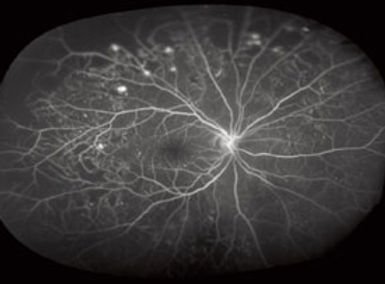

Green Laser (Photocoagulation): Green laser treatment is used to manage conditions like diabetic retinopathy and retinal vein occlusions. It involves directing a focused beam of green laser light onto the retina to seal leaking blood vessels or remove abnormal growths.

Diabetic Retinopathy: Causes and Treatment

Diabetic retinopathy is a diabetes-related eye condition that damages the blood vessels in the retina. It can occur in individuals with both Type 1 and Type 2 diabetes. Causes of diabetic retinopathy include:

Treatment for diabetic retinopathy may involve laser photocoagulation, anti-VEGF injections (such as bevacizumab, ranibizumab, or aflibercept), or vitrectomy. Early detection and management are crucial in preventing vision loss.